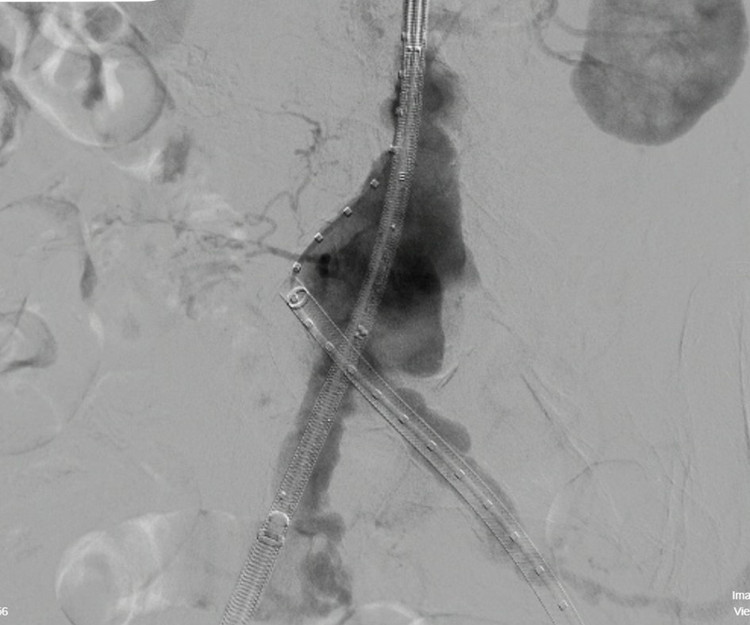

Sau hội chẩn chuyên môn, ê-kíp bác sĩ quyết định thực hiện đặt Stent Graft động mạch chủ bụng dưới hướng dẫn của hệ thống DSA.

Phương pháp can thiệp này chỉ gây tê tại chỗ, tiền mê nhẹ. Sau đó can thiệp qua đường động mạch đùi bằng một lỗ chấm nhỏ, tạo lòng mạch mới vững chắc, loại bỏ áp lực máu lên túi phình

Ca can thiệp diễn ra thuận lợi trong khoảng 1,5h. Bệnh nhân hồi phục nhanh, sinh hiệu ổn định và được xuất viện sau 3 ngày theo dõi, trong tình trạng sức khỏe tốt.

Can thiệp thành công ca bệnh - Ảnh BVCC